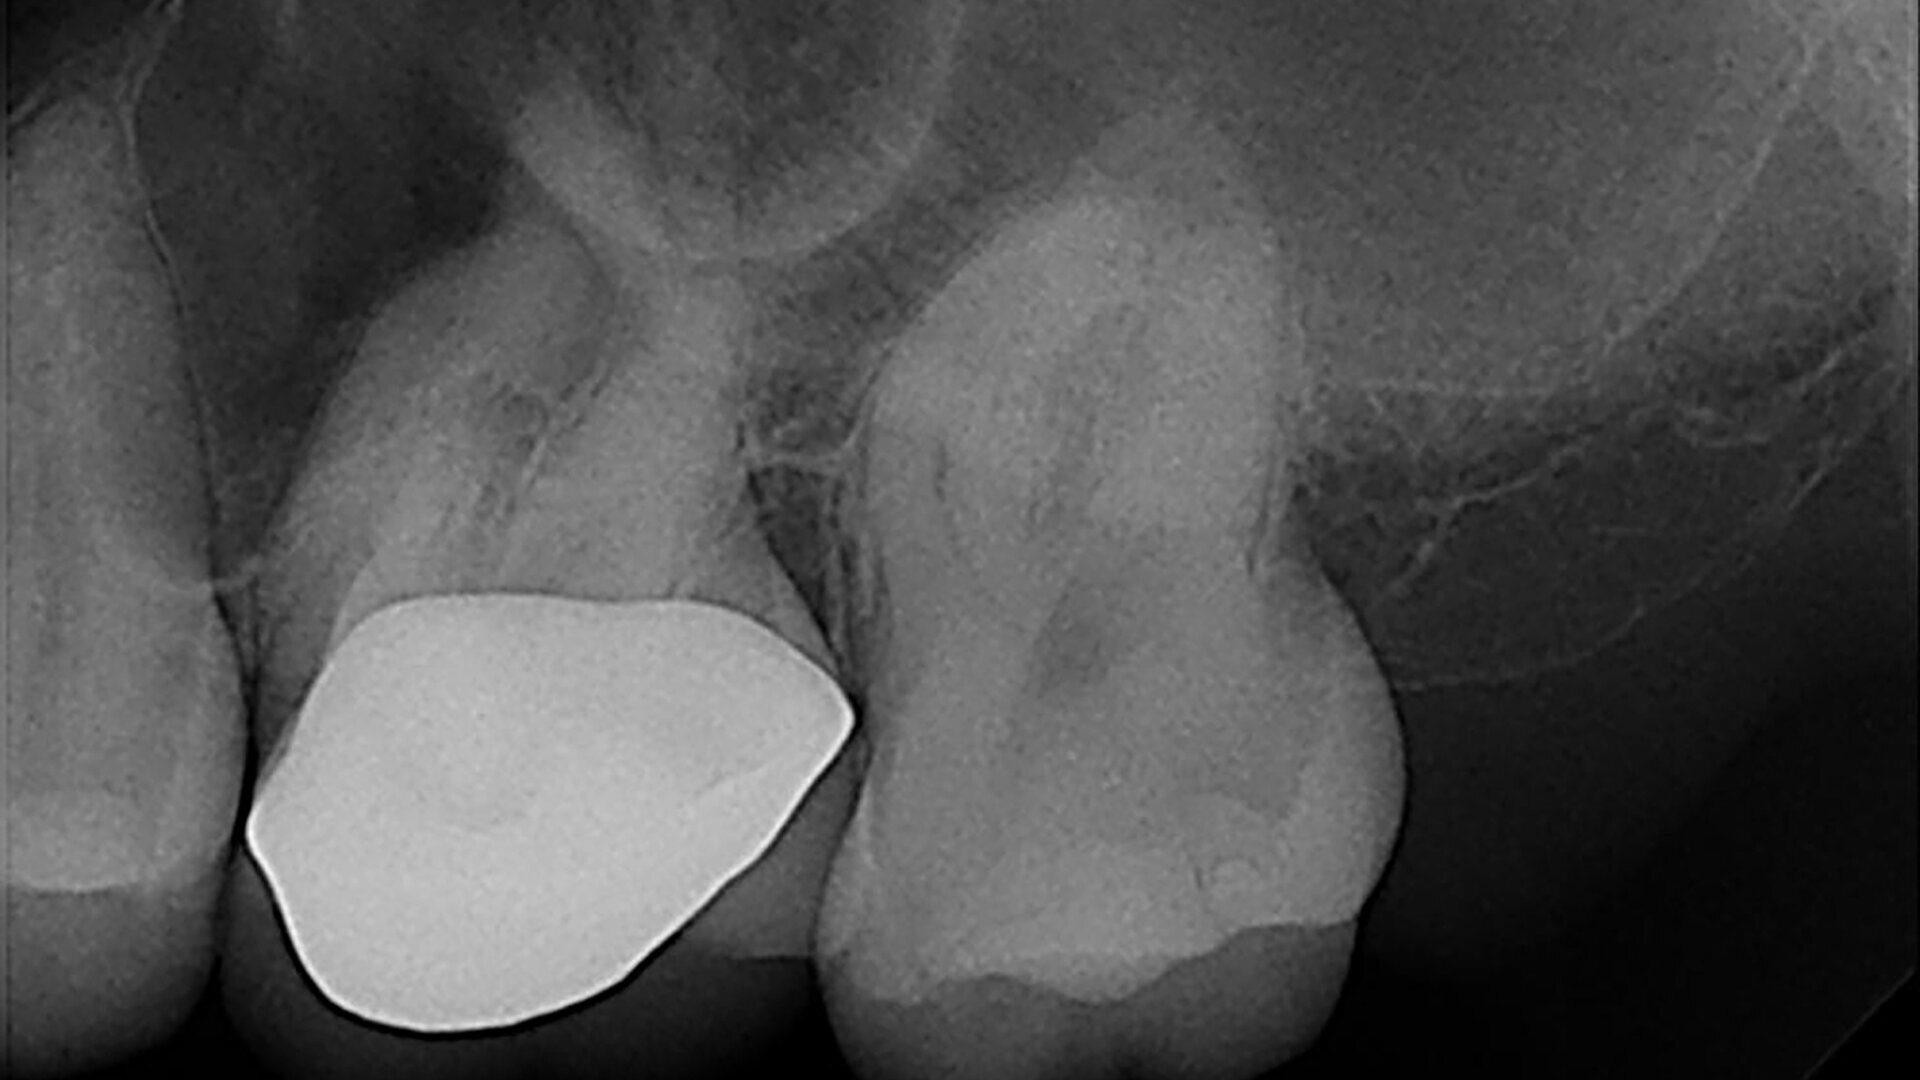

A 33-year-old patient with irreversible pulpitis and symptomatic periapical periodontitis affecting tooth #26. (Image: Dr Yanina Figueroa)

In this article, I report a case of a 33-year-old patient with irreversible pulpitis and symptomatic periapical periodontitis affecting tooth #26 (Fig. 1). This case was diagnosed and accessed through the crown using diamond burs and then irrigated with sodium hypochlorite.